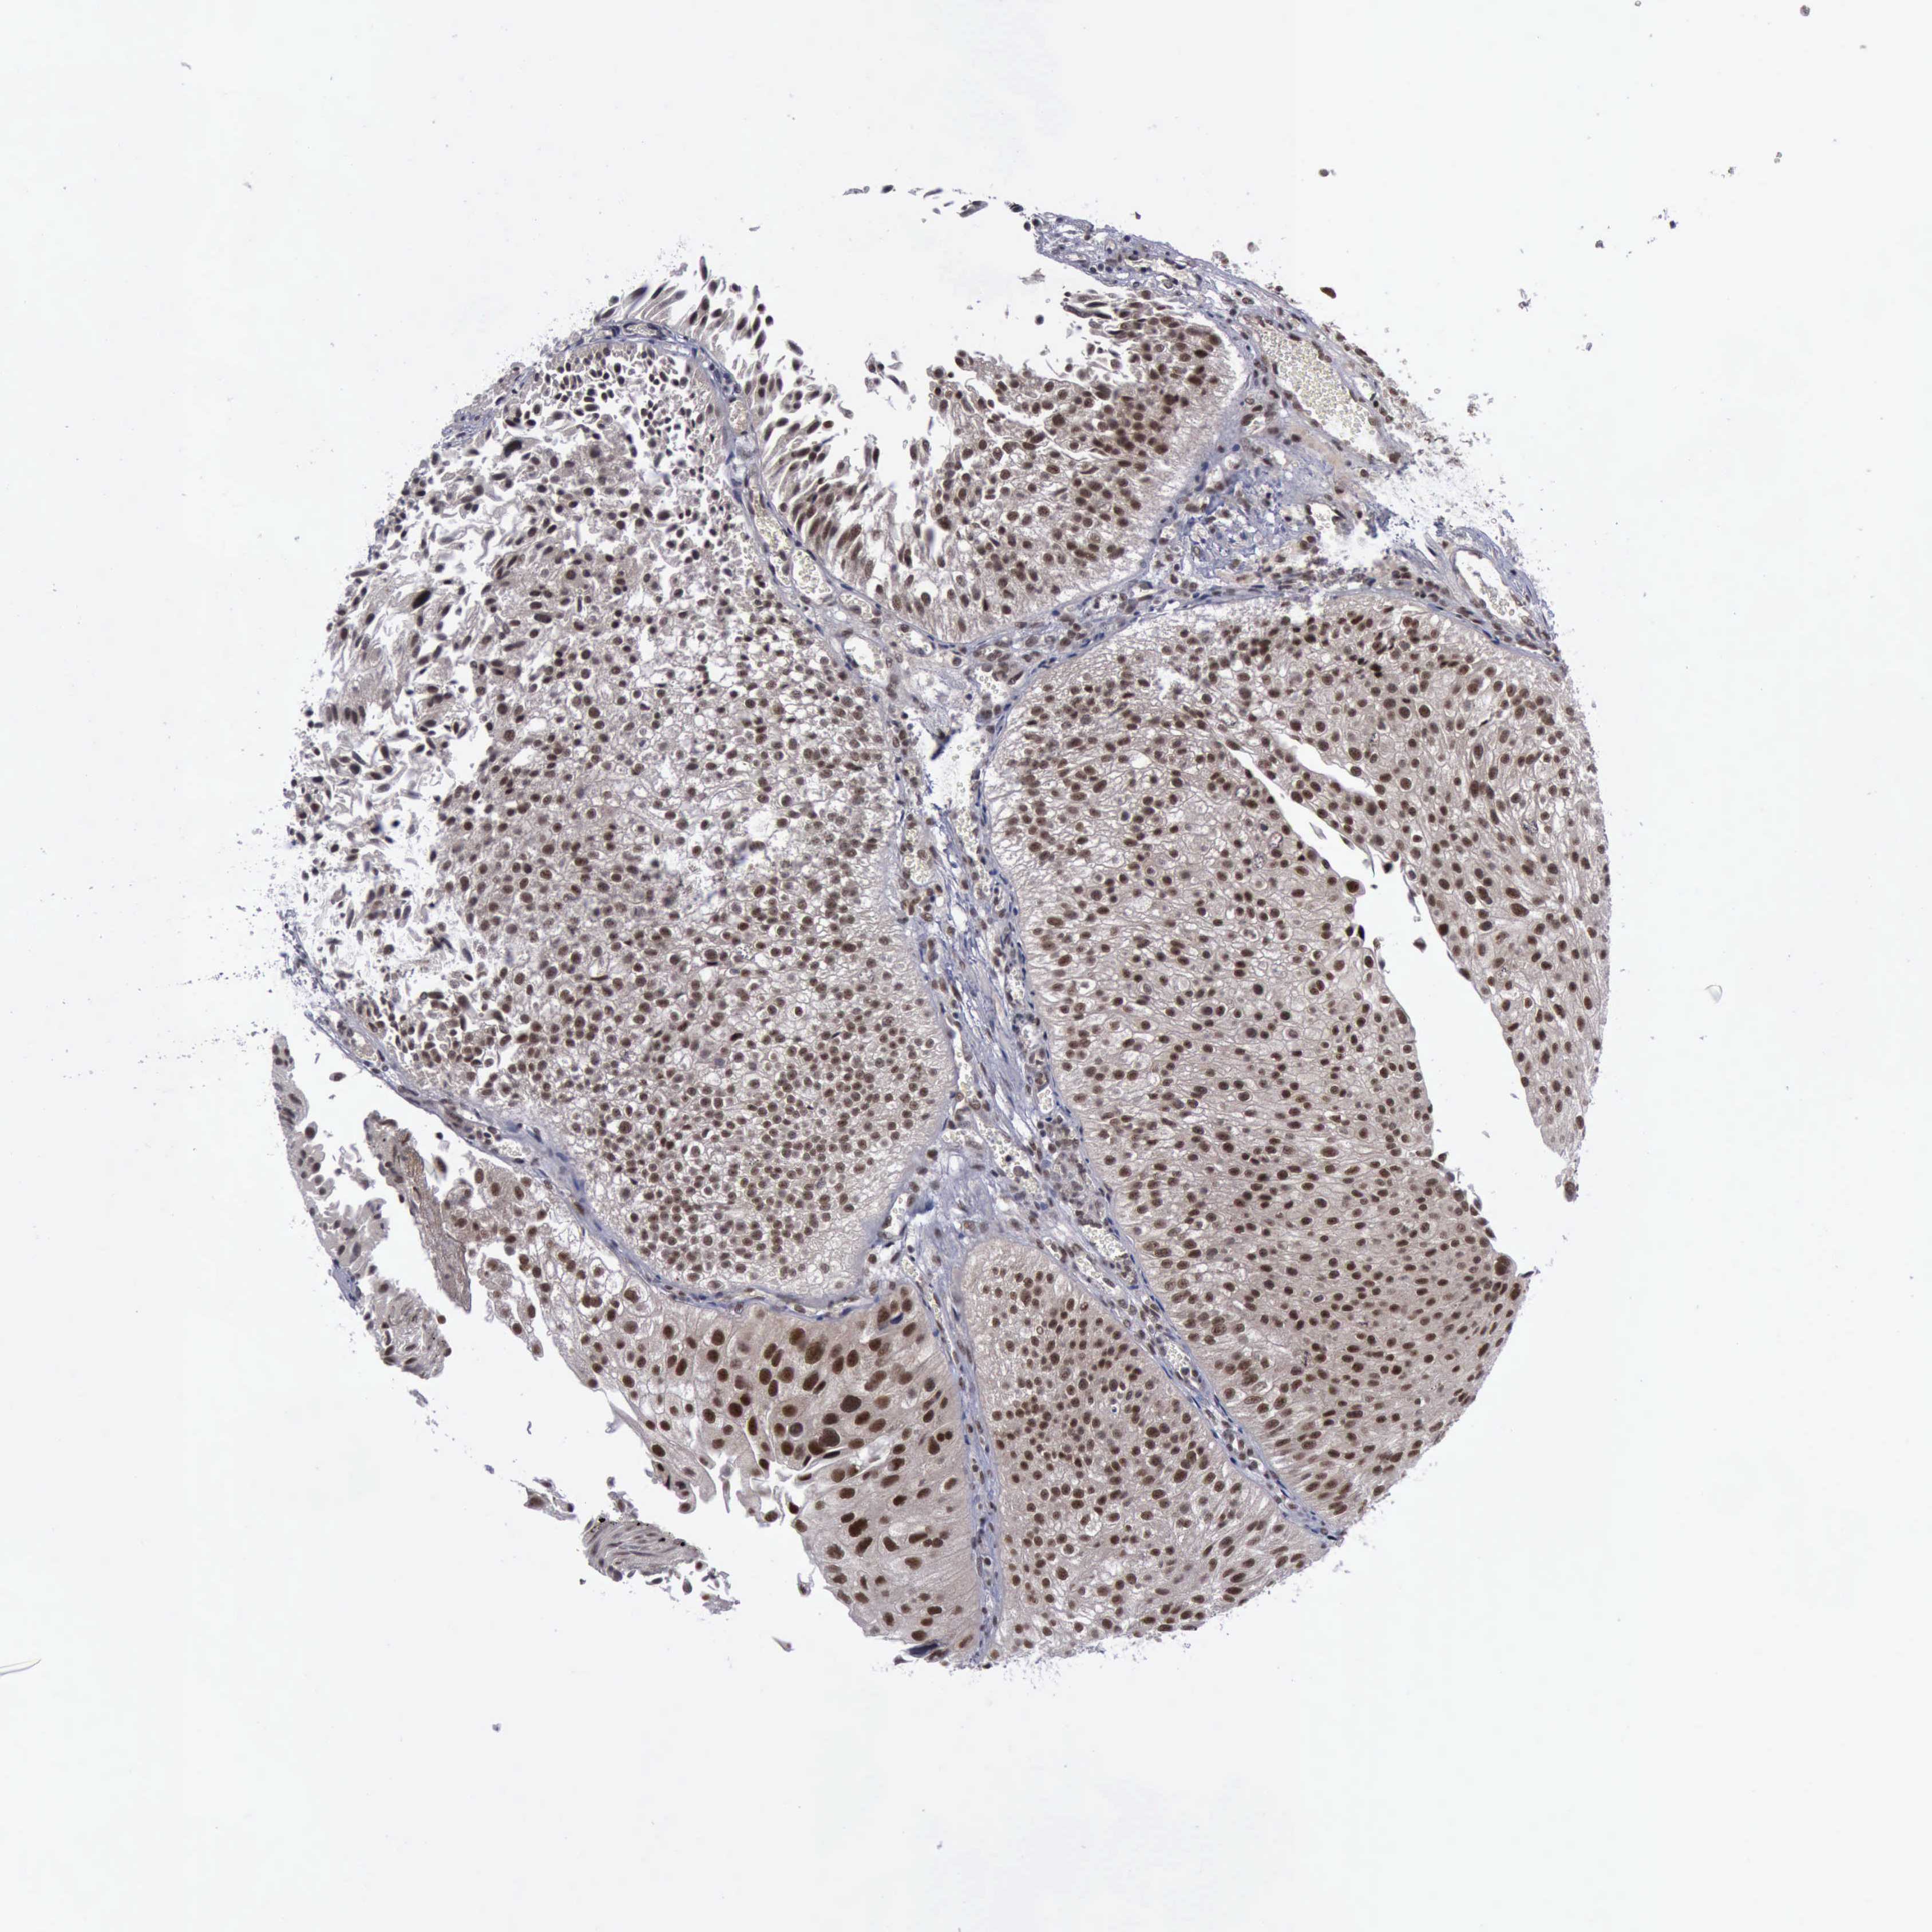

UROTHELIAL CANCER - Protein expressioni

A mouse-over function shows sample information and annotation data. Click on an image to view it in a full screen mode. Samples can be filtered based on level of antibody staining by selecting one or several of the following categories: high, medium, low and not detected. The assay and annotation is described here.

Antibody stainingi

Antibody staining in the annotated cell types in the current human tissue is reported as not detected, low, medium, or high, based on conventional immunohistochemistry profiling in selected tissues. This score is based on the combination of the staining intensity and fraction of stained cells.

Each image is clickable and will lead to virtual microscopy that enables deeper exploration of all samples and also displays staining intensity scores, fraction scores and subcellular localization as well as patient and tissue information for each sample.

Antibody CAB000102

Antibody CAB080442

Staining

High

Medium

Low

Not detected

Intensity

Strong

Moderate

Weak

Negative

Quantity

>75%

75%-25%

<25%

None

Location

Nuclear

Cytoplasmic/membranous

Cytoplasmic/membranous,nuclear

Adenocarcinoma, NOS